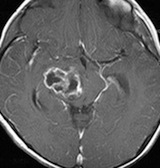

放射線治療13週目

右はガドリニウム増強です。ステロイドとグリセオールの点滴では制御できませんでした。悪性神経膠腫の病名で保険適応があるアバスチン(ベバシズマブ 10mg / kg)の投与を開始しました。

アバスチン投与後15日目

たった2週間で劇的な改善が見られました。失語症と片麻痺や認知機能も改善しました。